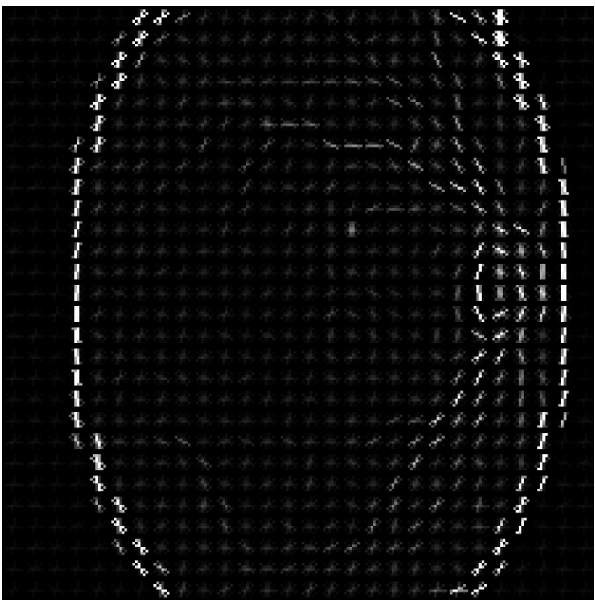

Refer to caption

(a)

(b)

(c)

Figure 4: Illustration of the preprocessing pipeline applied to a fundus image. From left to right: (a) Original color image, (b) grayscale conversion used for HOG computation, and (c) corresponding Histogram of Oriented Gradients (HOG) visualization highlighting edge and texture features.